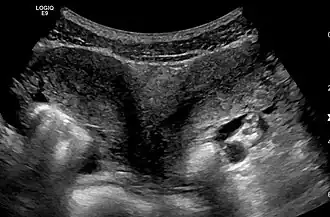

Uterus didelphys

Uterus didelphys[1], uterus didelphus[2] of uterus didelphis is een aandoening waarbij de baarmoeder dubbel aangelegd is, zoals bij de nieren. Beide baarmoeders hebben allebei een eigen baarmoedermond en soms heeft de vrouw ook twee vagina's. Elke baarmoeder heeft zijn eigen eileider en een eigen eierstok.